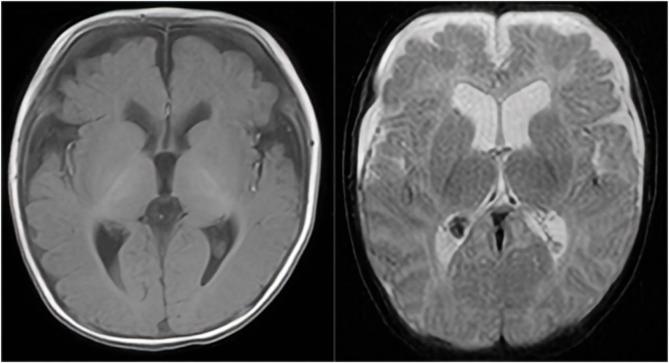

病例报告:一种新型FBXW7基因变异导致全面发育迟缓。

Case report: A novel FBXW7 gene variant causes global developmental delay.

To investigate a case of neurodevelopmental disorder caused by mutation of . Clinical data were collected from the patient, trio-WES (whole-exome sequencing) was performed on the patient and his parents (trio), and the results were verified by Sanger sequencing. RESULTS: The patient was a 2-year and 1-month old male who presented with facial dysmorphism (prominent forehead, ocular hypertelorism, and low nasal bridge), global developmental delay, language impairment, hypertonia, labial hemangioma, hydrocele, and overgrowth. The trio-WES confirmed that the child had a pathogenic gene variant, c.1612C>T (p.G1n538*), a heretofore unreported locus. This case of developmental delay, hypotonia, and impaired language (OMIM: #620012) related to a mutation in , is a rare genetic disorder, newly identified in recent years, and seldom reported. The presence of hypertonia, labial hemangioma, and hydrocele in this child suggests significant phenotypic heterogeneity of the disease, and the discovery of new mutant loci enriches the spectrum of pathogenic variants of the disease.

为调查一例由……突变引起的神经发育障碍病例。收集了该患者的临床资料,对患者及其父母进行了三联全外显子测序(trio-WES),并通过桑格测序对结果进行了验证。结果:该患者为一名2岁1个月大的男性,表现为面部畸形(前额突出、眼距增宽、鼻梁低平)、全面发育迟缓、语言障碍、肌张力亢进、唇部血管瘤、鞘膜积液和生长过速。三联全外显子测序证实该患儿有一个致病基因变异,c.1612C>T(p.Gln538*),这是一个此前未报道的位点。这例与……突变相关的发育迟缓、肌张力减退和语言障碍(OMIM:#620012)病例是一种近年来新发现的罕见遗传病,鲜有报道。该患儿存在肌张力亢进、唇部血管瘤和鞘膜积液,提示该病具有显著的表型异质性,新突变位点的发现丰富了该病的致病变异体谱。